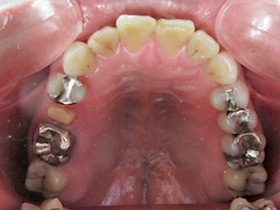

20代女性

今まで歯科が怖くて行けず、放置していた。前歯が痛くて来院。奥歯でも噛めず、前歯も綺麗にしたいと来院。今回は完治したい。

最初にインフォームドコンセントをしっかり行いました。それは、患者さんの協力無しでは治療はできません。本気で治したい!自分の歯ですから!と歯医者まかせではなく、歯科治療は患者さんとドクターとの共同作業になりますから。

まず虫歯で壊れている歯は根の先まで膿んでいたため、根管治療後、歯肉整形をしファイバーコアを使い土台を作りました。全ての歯を抜かずに残す事ができました。被せ物はメタルボンドを希望されてましたのでメタルボンドにて修復しました。この方は元々開口(オープンバイト)であった為上下が噛んでなかったため下の歯が生えてきた時と同じ形態を維持してたため審美的に上の歯並びをどうしたいかを相談したら下と同じ様に元々の状態に回復して欲しいと希望されましたので、その様に治療しました。奥歯も保険にて全て治療完成しました。

患者さんはちゃんと噛める様になった事と、長年放置してて無かった前歯が入りすごく喜んでもらえました。これで口元を気にしないで大口でも笑えますね。